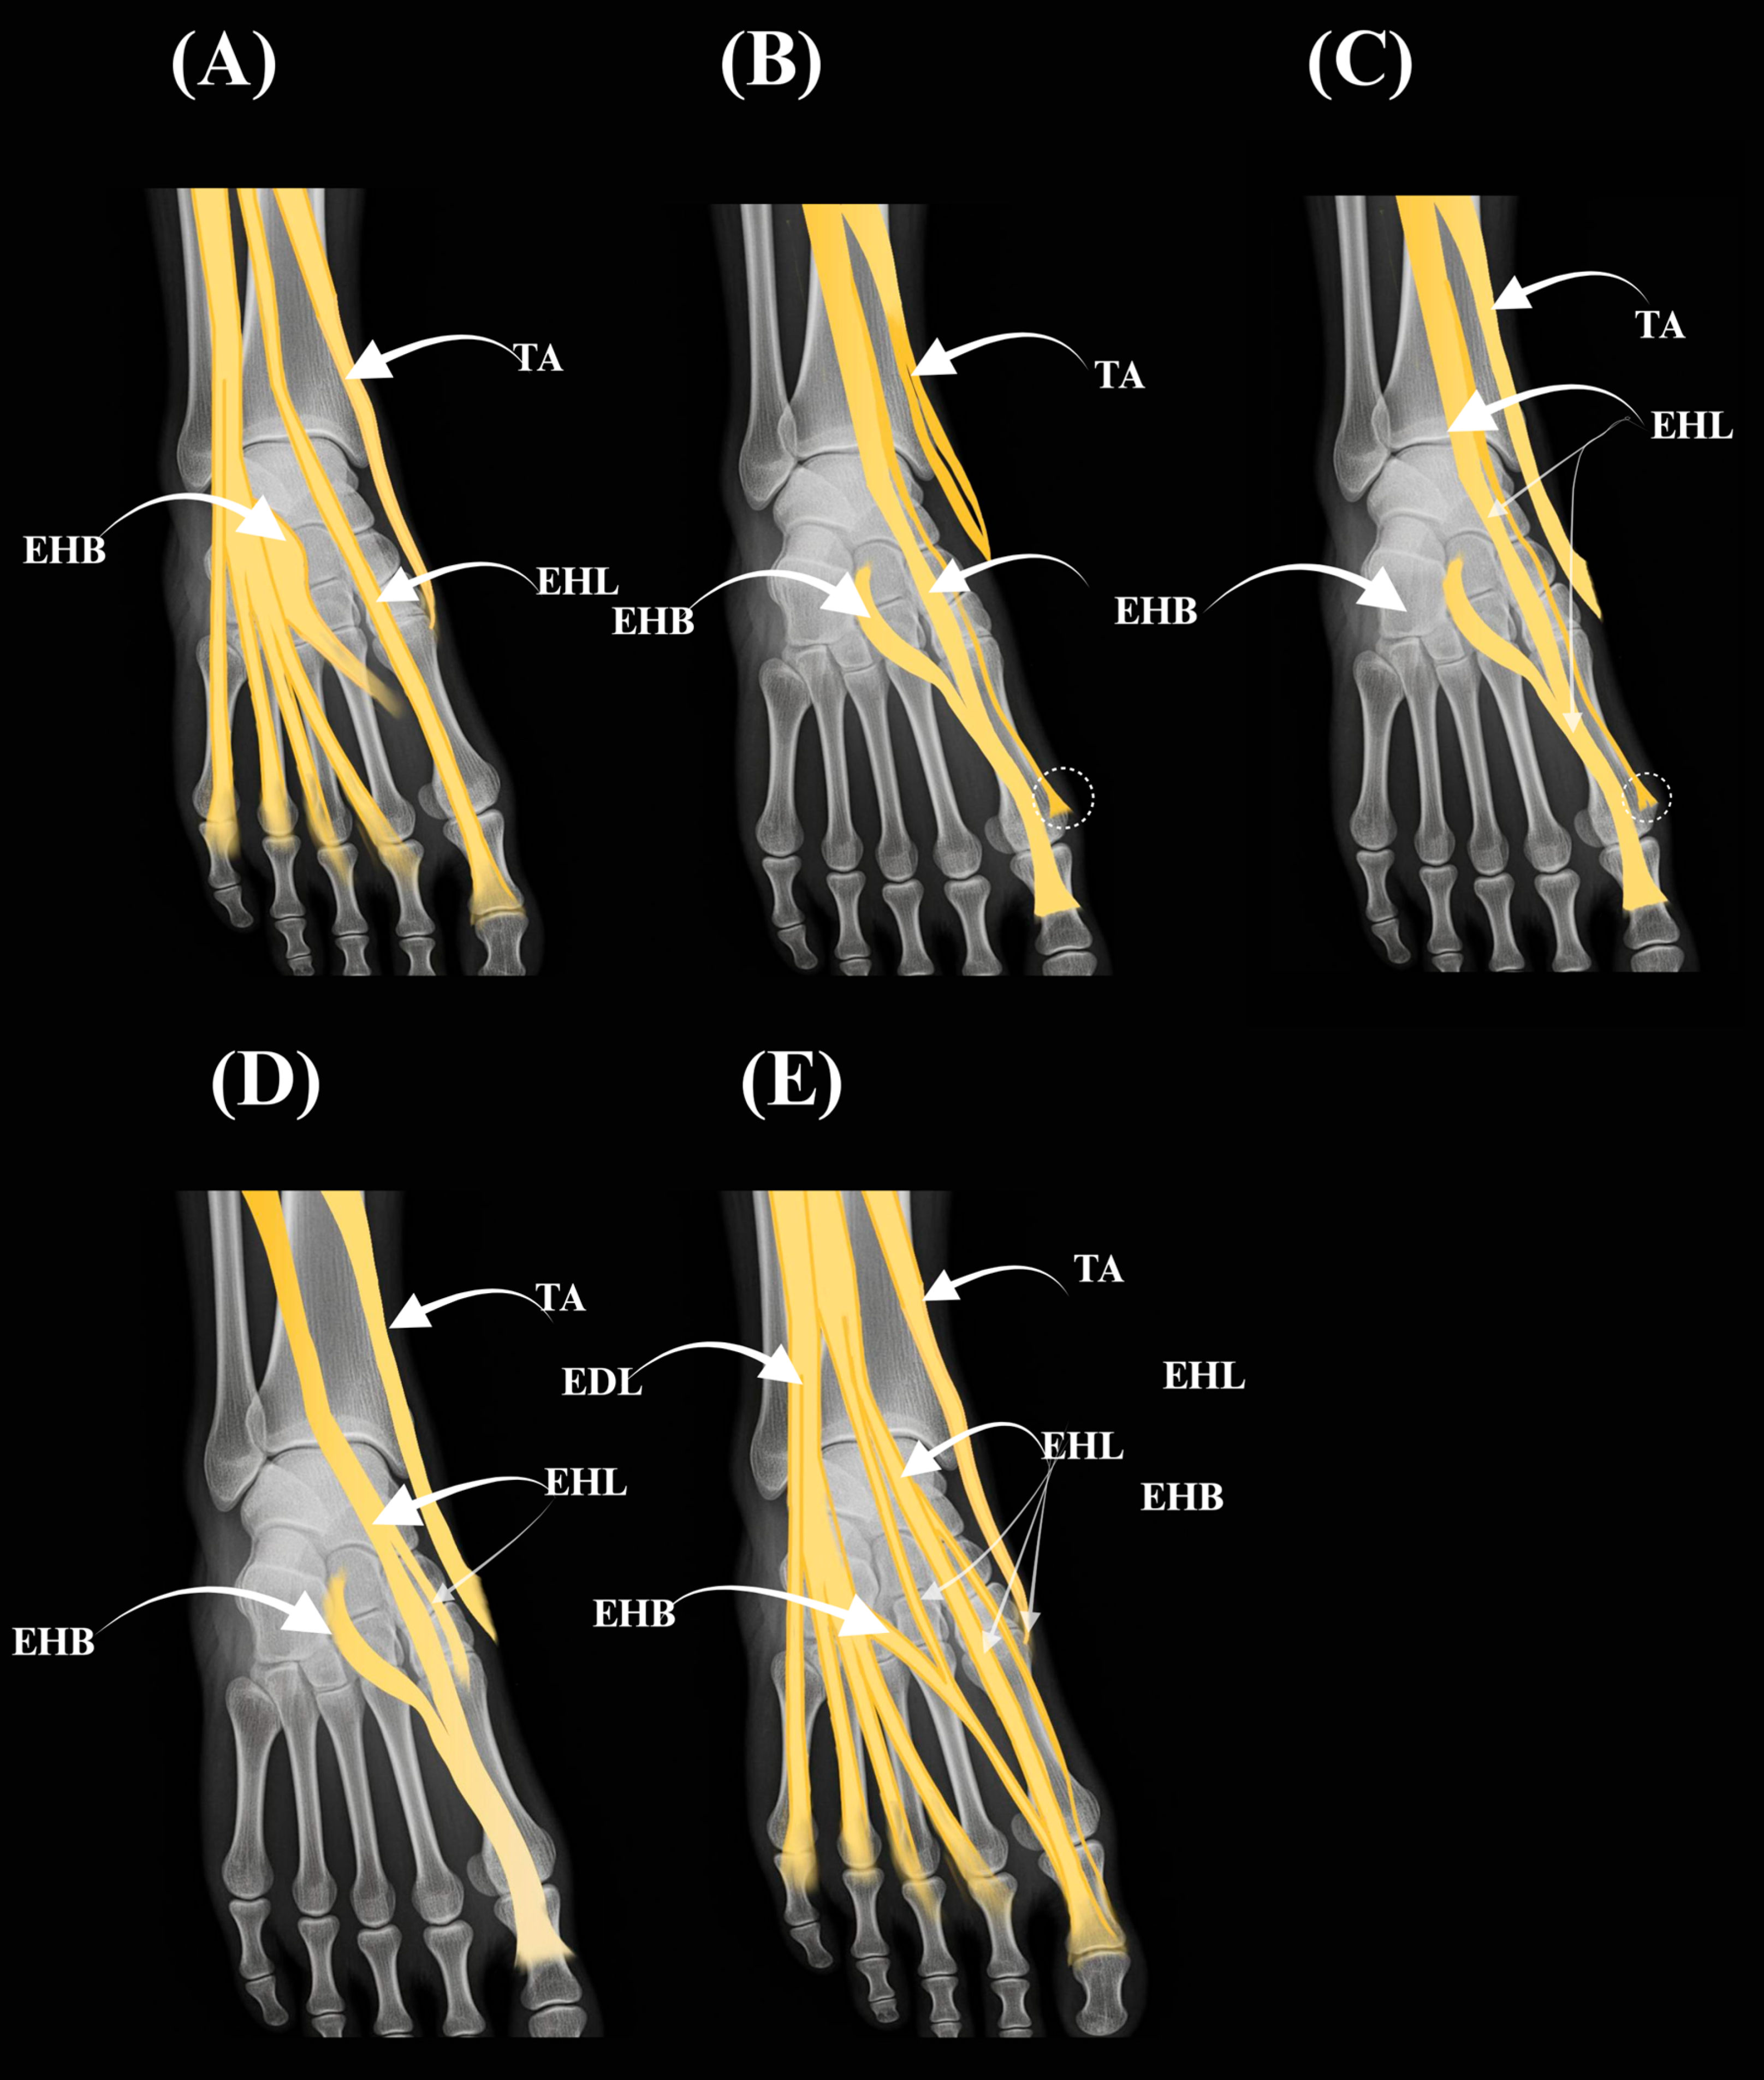

A schematic atlas of the Olewnik et al. [1] variants is provided in Figure 2 (panels A–E).

Figure 2. Atlas of extensor hallucis longus (EHL) tendon variants according to (Olewnik et al. [1]) Types I–III with subtypes IIa–IIc are illustrated as simplified overlays on a dorsum-of-foot template. (A) Type I (single slip to the distal phalanx). (B) Type IIa (two slips; accessory slip inserting into the proximal phalanx; dashed circle). (C) Type IIc (two slips; accessory slip inserting into the base of the first metatarsal; dashed circle). (D) Type IIb (two slips; bifid accessory at the proximal phalanx). (E) Type III (three slips). Arrows indicate insertions and course. Abbreviations: EHB—extensor hallucis brevis; EDL—extensor digitorum longus; TA—tibialis anterior.